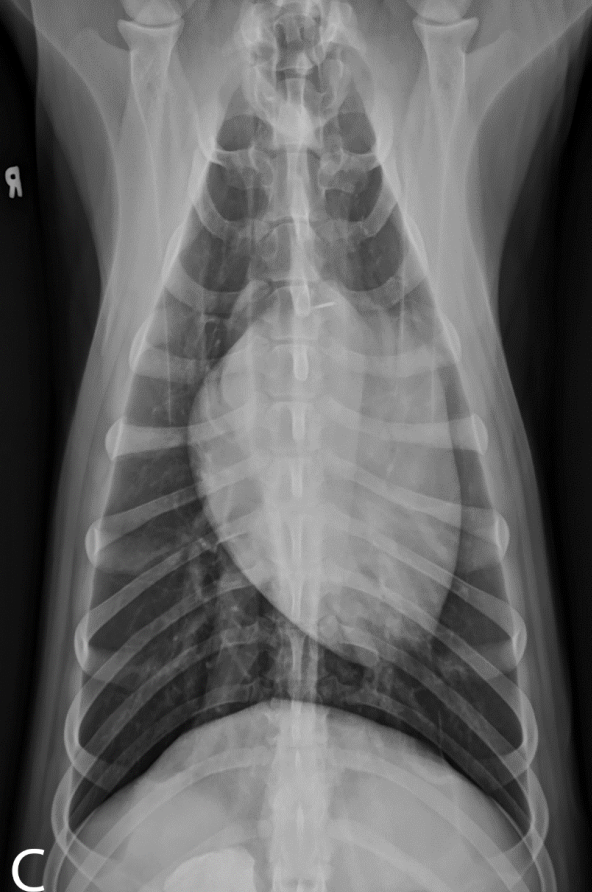

What is shown in these images?

A

generalized lymphadenopathy:

-widening of mediastinum

-deviation of mainstem bronchi